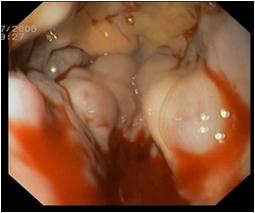

A nyelôcsô- és gyomor varixokból eredô tápcsatornai vérzések korszerű ellátásnak bemutatása.